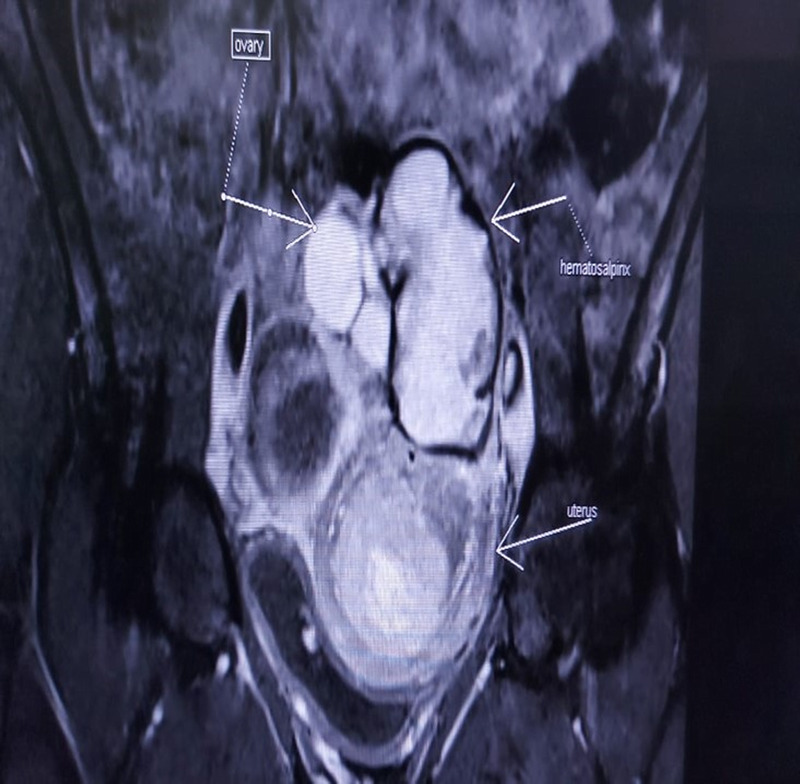

The disorder of sex development is a rare disorder that usually occurs in early childhood. As adults, those with disorder of sexual development present with gynecomastia, primary amenorrhea, and primary infertility, which often causes great psychological impact. We report a unique case of a male adult hermaphrodite presenting with hematometra and hematosalpinx. Early management including psychiatry counseling, gender reassignment, and surgery is essential. Our patient underwent müllerian tissue removal with phallus reconstruction.